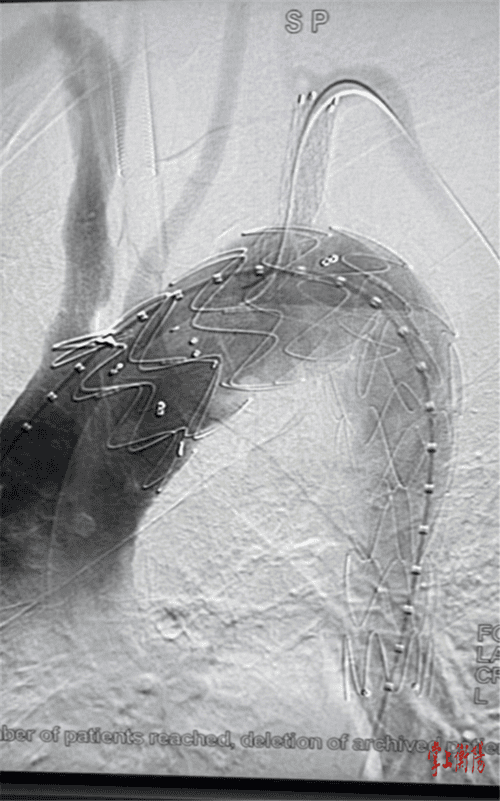

据悉,患者所患的是胸主动脉假性动脉瘤,病变累计供应头颅血运的弓部主动脉,随时有血管破裂大出血死亡风险,这种疾病是血管外科最为凶险、复杂的疾病。常规的开放手术需要开胸及体外循环,创伤大、并发症发生率高,对患者损伤较大。若采用介入技术,患者的弓动脉瘤足足有3公分大,由于弓部有重要分支血管,腔内治疗面临着巨大的挑战,稍有差池都可能影响大脑血供、导致脑梗等严重后果。最终,南华附二医院血管外科团队经过反复推敲和论证,在上海长海医院专家的远程会诊指导下,决定采用体外预开窗的方式,术前根据影像资料确定病变部位与分支血管之间的关系,体外将预制支架部分释放,精准定位后在支架上预先开好两个窗用来重建颅内两分支血管,术中准确释放支架,保证支架和窗口的精确对应,保障大脑血运不受影响。

最终,手术历时近3个小时,顺利为患者放入了覆膜支架,隔绝了胸主动脉弓部的“炸弹”。此次远程手术中,协调指导几乎完全同步,手术过程中网络零延时,来自上海的专家仿佛亲临现场指导一样,效果很好。手术的成功实施,让患者避免了开胸手术带来的损伤,也减少了医疗费用,加速了患者的术后康复。